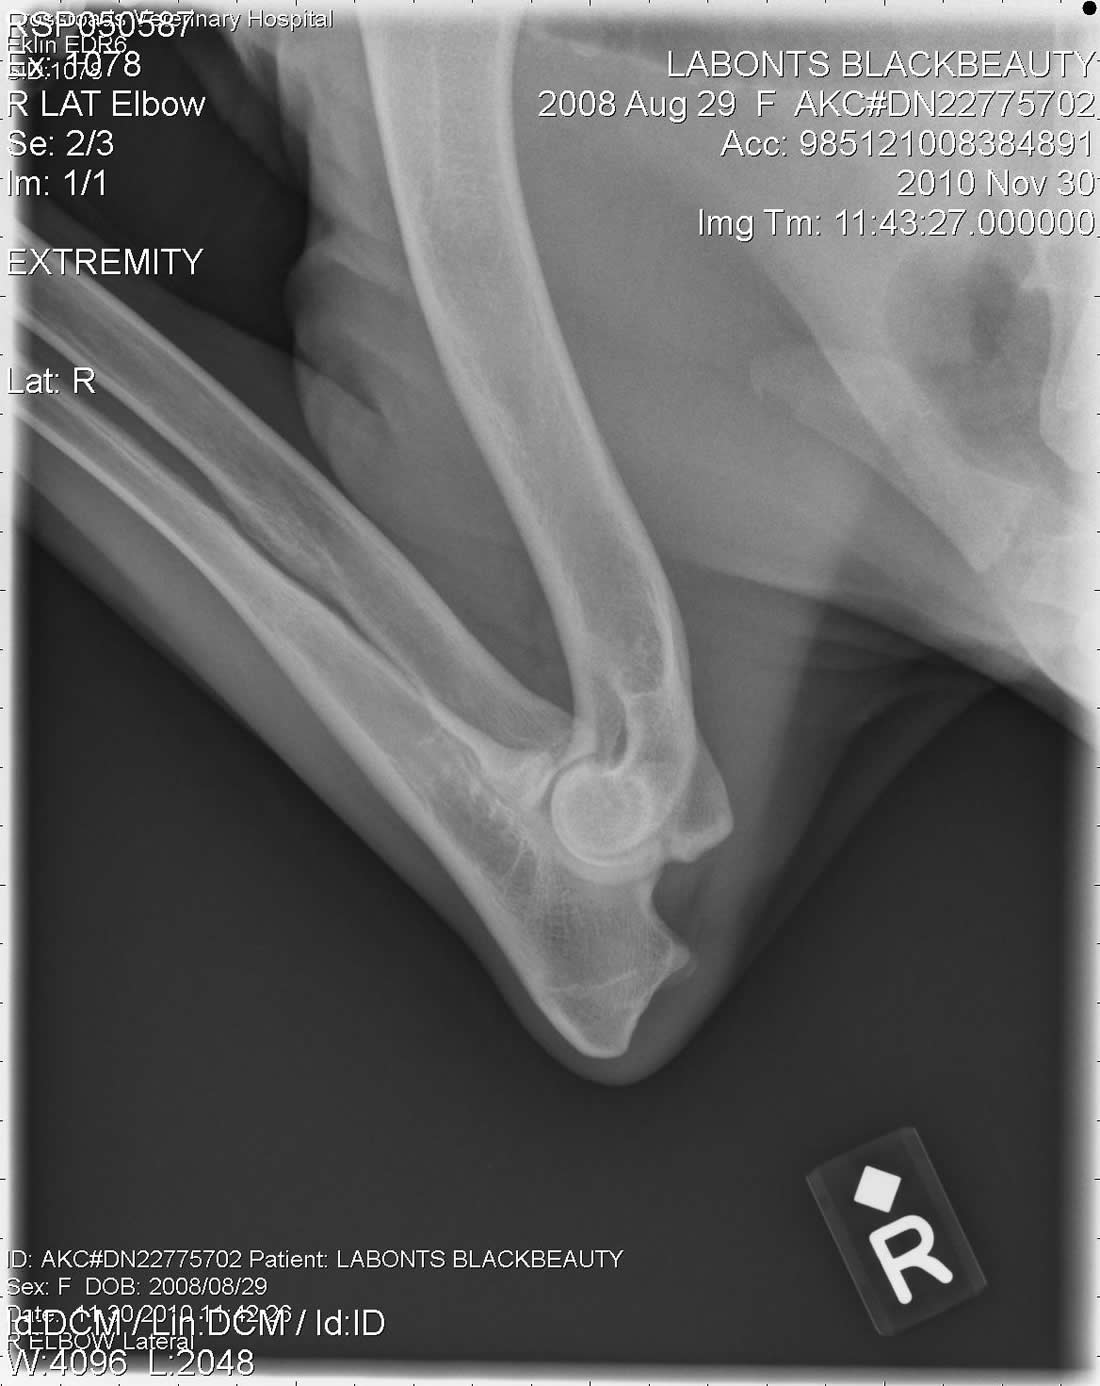

Tilly OFA - Female Working German ShepherdLabonte's Black Beauty (Tilly) OFA Excellent is an extreme prey driven dog. Her hips have the rare OFA rating of Excellent. She is black and has an awesome muscular European structure. Tilly pedigree is nothing short of awesome. With dogs like Fero, Quinto, Orry and lines like Karthago, Antverpa, Tiekerhook, Korbelbach giving her a very well rounded foundation and strong genes for breeding. Click here for Tilly's pedigree